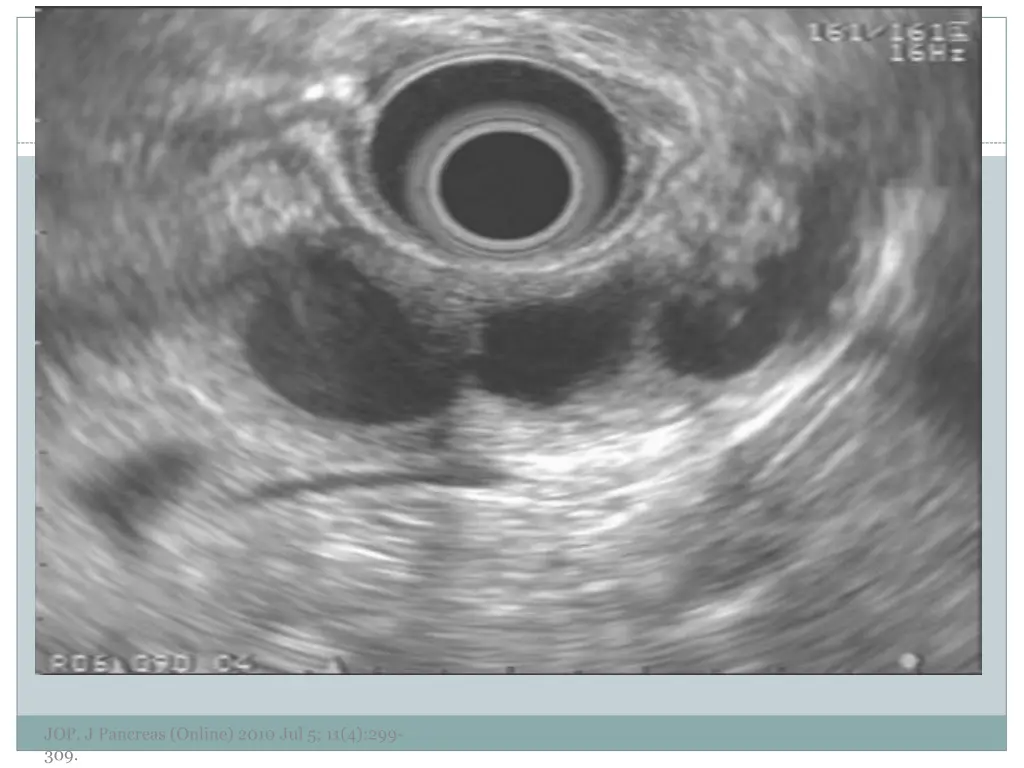

7. EUS Morphology Cyst wall Thick vs. thin Solid component Associated with malignancy Septations Micro vs. macrocystic Ductal abnormalities Main duct vs. side duct Number of cyst Lymphadenopathy EUS morphology can correctly differentiate mucinous from non-mucinous cystic lesions approximately 50% of the time JOP. J Pancreas (Online) 2010 Jul 5; 11(4):299- 309.

10. Examples of Morphology JOP. J Pancreas (Online) 2010 Jul 5; 11(4):299- 309.

11. JOP. J Pancreas (Online) 2010 Jul 5; 11(4):299- 309.